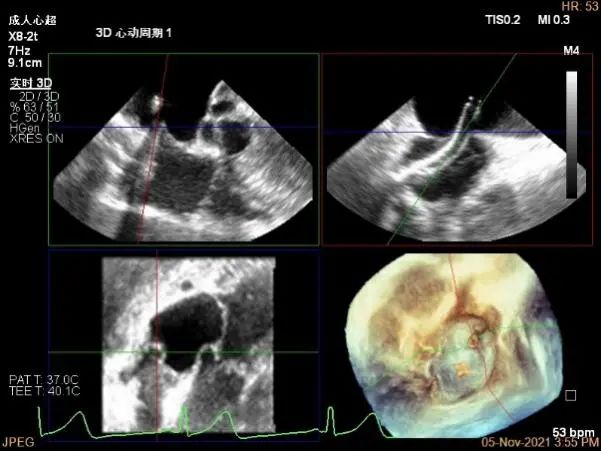

术前超声评估结果

术前超声诊断

二尖瓣瓣环前后径26mm,左右径26mm

Bicom:MR(重度),返流束宽12.5mm,返流面积11.4cm²

PISA法定量EROA:0.74cm²,Rvol:118ml,RF:63%

右上肺静脉血流频谱呈收缩期反向

3D MV View:A2/A1区脱垂

3D-color MV view:血流主要来源于A2区,少部分来源于A1区

Qlab软件勾画估测瓣口面积约:5.6cm²

二尖瓣口平均跨瓣压差:4mmHg

TEE Bicom view:主要脱垂区域为2区

Color-view:返流束主要来源于2区脱垂

A1P1区后叶发育短小,约5.3mm

A2P2区前后叶长度可,为主要脱垂区域,进而制定手术策略: 2区一个长夹子解决脱垂主要病变区域